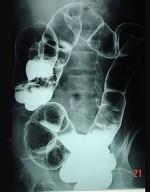

问题 男,70岁,右下腹胀,腹痛,腹泻,影像检查如图,最可能的诊断是 ( )

选项 A、结肠结核 B、结肠淋巴瘤 C、结肠癌 D、结肠套叠 E、结肠克隆恩病

答案 C